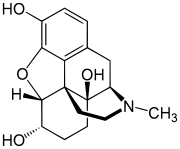

The pharmacodynamic response to an opioid depends upon the receptor to which it binds, its affinity for that receptor, and whether the opioid is an agonist or an antagonist. For example, the supraspinal analgesic properties of the opioid agonist morphine are mediated by activation of the μ1 receptor; respiratory depression and physical dependence by the μ2 receptor; and sedation and spinal analgesia by the κ receptor. Each group of opioid receptors elicits a distinct set of neurological responses, with the receptor subtypes (such as μ1 and μ2 for example) providing even more [measurably] specific responses. Unique to each opioid is its distinct binding affinity to the various classes of opioid receptors (e.g. the μ, κ, and δ opioid receptors are activated at different magnitudes according to the specific receptor binding affinities of the opioid). For example, the opiate alkaloid morphine exhibits high-affinity binding to the μ-opioid receptor, while ketazocine exhibits high affinity to ĸ receptors. It is this combinatorial mechanism that allows for such a wide class of opioids and molecular designs to exist, each with its own unique effect profile. Their individual molecular structure is also responsible for their different duration of action, whereby metabolic breakdown (such as N-dealkylation) is responsible for opioid metabolism.

Several semi-synthetic opioids were developed in Germany in the 1910s. The first, oxymorphone, was synthesized from thebaine, an opioid alkaloid in opium poppies, in 1914.[228] Next, Martin Freund and Edmund Speyer developed oxycodone, also from thebaine, at the University of Frankfurt in 1916.[229] In 1920, hydrocodone was prepared by Carl Mannich and Helene Löwenheim, deriving it from codeine. In 1924, hydromorphone was synthesized by adding hydrogen to morphine. Etorphine was synthesized in 1960, from the oripavine in opium poppy straw. Buprenorphine was discovered in 1972.[228]